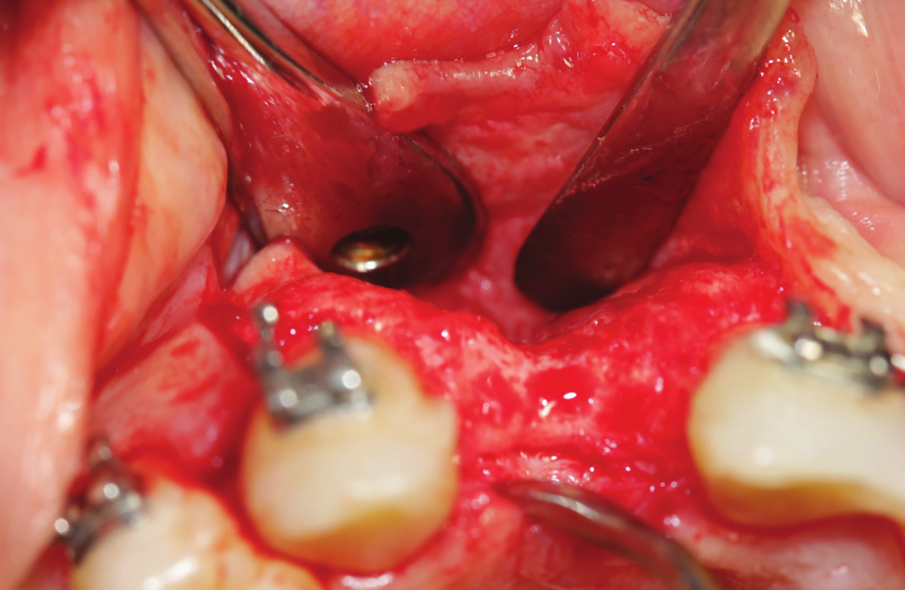

Figure 22: Inter operative view after reflection of mucoperiosteal flap, showing the extended amount of bone loss with intralesional secretion bulging outside the bone cavity.

Figure 23: Enucleation of the 1.5 cm lesion followed by extraction of endodontically perforated tooth no 7.

Figure 24: Bone cavity showing extended bone loss.

A 38 years-old female patient came to our clinic with swelling upper anterior area, she was medically fit with no health problems. The patient underwent an orthodontic treatment for 2 years and was about to remove it and place retainer. Intraoral examination showed swelling apical area of tooth no 7. The periapical x-ray and CAT view revealed a lateral perforation on the same mentioned tooth with a well circumscribed radiolucency in apical area (Fig.20, 21). Pain on percussion and slight mobility were noted. A surgical enucleation and extraction of tooth no 7 were conducted (Fig.22, 23, 24). 3 months postoperative CAT view shows an advanced horizontal bone loss with no recurrence of lesion in the area (Fig. 26), clinically after reflection of mucoperiosteal flap, the situation confirmed the CAT image (Fig.25) , the case was planned for PRF -associated bovine bone technique replacing the aggressive autologous bone graft procedure. After collection of PRF from patient blood culture, a first layer of L-PRF covering the bovine bone associated PRF complex (sticky bone) was done (Fig.27). The second layer of L-PRF came to cover the cross-linked collagen membrane (Fig. 28).